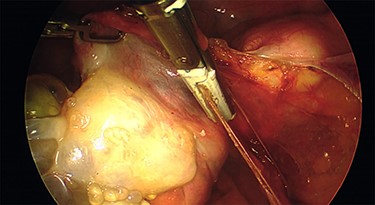

Intraoperative findings were inconsistent with all pre-operative ultrasound diagnoses. Both ovaries appeared suspicious for malignancy with cystic lesions covering the surface of the right, while the left appeared to contain two smaller cysts (Figs 3–5). There were no hydrosaplinges or free fluid within the pelvis. Given the abnormal features of the ovaries, the surgeon proceeded with the laparoscopic BSO without spillage. Pelvic washings were performed, though there were no atypical peritoneal or omental lesions for biopsy.

The intra-operative photos demonstrating the cystic appearance of the left ovary.

The intra-operative photos demonstrating multiple cystic structures covering the surface of the right ovary.

The intra-operative photographs of the posterior aspect of the right ovary.